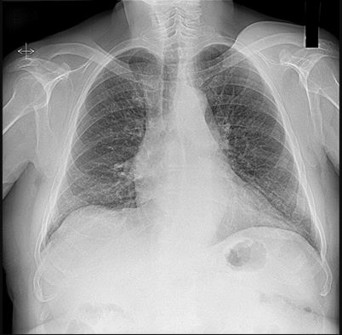

Figures 5a and 5b are the radiographs of a 74-year-old man with poorly differentiated squamous cell carcinoma of the lung. He has had an uneventful recovery after undergoing a wedge resection of his left upper lobe 6 months ago. He is experiencing left lateral knee pain, and a whole-body positron emission tomography/CT scan shows no avid area other than the lateral left distal femur. This patient has needed to use a wheelchair for 3 weeks because of his pain. You discuss these treatment options: aggressive curettage, local adjuvant treatment, cementation, and prophylactic fixation vs distal femoral resection and megaprosthesis total knee arthroplasty reconstruction. You should tell him that

Distal femoral megaprosthetic reconstruction after tumor resection is a reliable oncologic procedure, but 5-year implant survival is as low as 74% with an approximate 8% deep infection rate. The amputation rate is as high as 8% because of infection or recurrence, and there is an overall 18% revision rate. More than 10% of distal femoral megaprosthetic reconstructions are performed to address metastatic disease.

Fixation failure and infection may occur with either procedure. Radiation may not be recommended after a megaprosthesis reconstruction unless margins are not free of tumor. Either operation may be equally successful in returning patients to functional activities. Overall disease-free survival is related to the aggressiveness of the tumor and not the type of reconstruction performed.